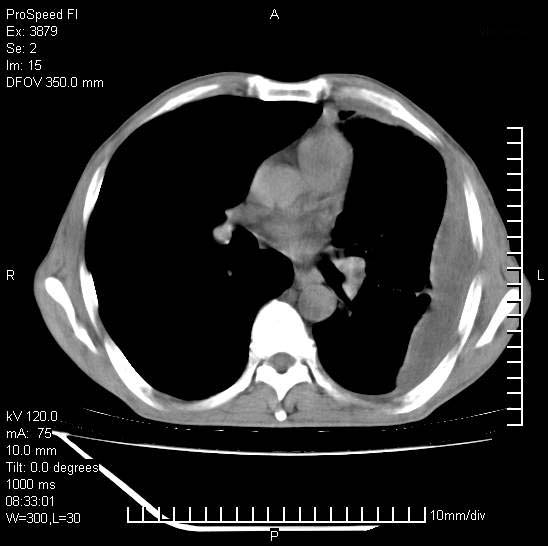

以下是引用37度在2008-6-6 11:20:00的发言:[br]1.包裹性积液,多考虑结核性;[br]2.穿刺术后改变。

以下是引用312nanyang在2008-6-6 15:12:00的发言:[br]基本支持楼主意见[br]疑问?左下肺支气管旁的软组织(16层)密度怎么解释?淋巴结还是斜裂胸膜增厚所致?能否增强进一步检查